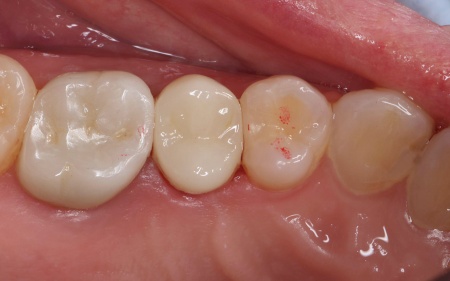

1:細菌感染した神経を取り除いてから薬を詰める「根管治療」 2:歯を長く使えるように土台をたてる「支台築造」 3:被せ物による「補綴修復」 以上のメリットとデメリットを丁寧にお伝えし、治療に同意いただきました。 まず、割れている部分をしっかりと確認し、必要な部分を除去してから根管治療を行います。 最後に、完成した被せ物を装着し、噛み合わせや見た目に問題がないことを確認して、治療を終了しています。 なお、患者様の下の歯の治療についてはこちら:https://dr-kaiya.com/blog/20260312-2/ |

治療後